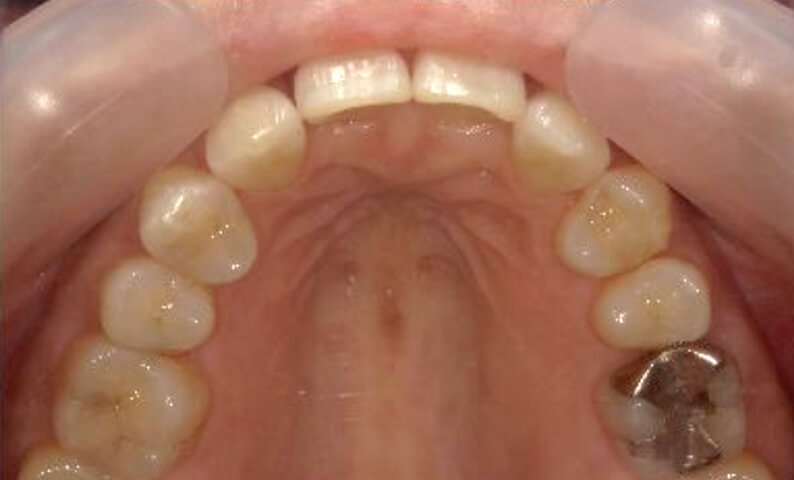

症例_022 上下顎の部分矯正

治療期間:9ヶ月金額:51万円+税女性前歯のガタガタ八重歯

| Before | After |